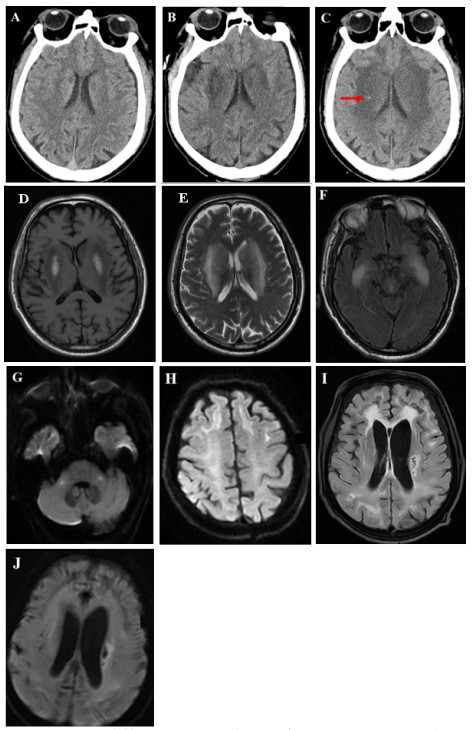

1 病例资料患者男,67岁,既往有糖尿病史,2023-07-05口服农药哒螨灵约50 mL,具体浓度不详。服药10 h后出现行走不稳,被家属送至当地医院行清水洗胃10 000 mL,随后出现意识不清、血压下降,诊断为急性哒螨灵中毒并紧急转至我院。入急诊查体:血压65/40 mmHg(1 mmHg=0.133 kPa),深昏迷,格拉斯哥昏迷指数(GCS)3分(E1V1M1), 双侧瞳孔等大等圆,直径3 mm,对光反射迟钝,颈软,双侧鼻唇沟对称。双肺呼吸音粗,未闻及啰音。心律齐,心率103次/min。生理反射存在,病理反射未引出。完善实验室检查,动脉血气分析:pH 6.973,氧分压112.4 mmHg,二氧化碳分压22.6 mmHg,乳酸15.5 mmol/L;血常规:白细胞计数25.81×109/L, 中性粒细胞百分比80.9 %;生化指标:丙氨酸氨基转移酶62.0 U/L,门冬氨酸氨基转移酶129.0 U/L,肌酐151.30 umol/L;心肌损伤标记物:肌钙蛋白I 1.24 ng/mL,肌酸激酶同工酶16.03ng/mL,肌红蛋白 > 600.0 ng/mL。血液药物浓度检测(采用液相-质谱联1用仪):哒螨灵浓度为120 ng/mL。入院后立即行气管插管接呼吸机辅助呼吸、多巴胺泵入升压[8 ug/(kg·min)]。入院当日胸部CT:两肺少许炎症、渗出,右侧胸腔少量积液。头颅CT:双侧脑室旁见对称性月晕状稍低密度影,颅内多发缺血灶,见图 1A。

| 注:(A)入院第1天CT示双侧脑室旁见对称性月晕状稍低密度影;(B)入院第5天CT示双侧基底节区对称性低密度灶,较前显著;(C)入院第15天CT示双侧基底节区病灶较前密度减低,新增小片状高密底影,提示小出血灶(箭头所示);(D-H)入院第9天MRI示双侧基底节区呈对称性长T1长T2信号,伴有脑肿胀;FLAIR序列双侧颞叶深部对称性高信号影;DWI序列双侧桥臂、额叶皮层下白质多发斑点片状及条片状高信号影;(I-J)出院第6个月MRI示FLAIR和DWI序列双侧基底节区仍见多发斑点状及条片状异常信号影,较前高信号减低,范围缩小,脑室系统明显扩大,皮层萎缩 图 1 本例患者头颅影像学动态演变 |

患者入院后即行血液灌流(3次/d,共2 d)清除毒物、连续性肾脏替代治疗纠正内环境紊乱、血管活性药物维持血压、补液促进毒物排泄及对症支持等治疗。中毒后第5天,患者仍深昏迷,GCS评分2T(E1VTM1)。复查头颅CT:双侧基底节区对称性低密度灶,较前片明显,见图 1B。中毒后第9天,意识状况仍无改善,检查头颅MRI:双侧额顶颞枕叶皮层下、基底节区、桥臂多发异常信号,伴脑肿胀,考虑中毒性脑病,见图 1D~图 1H;磁共振动脉自旋标记(arterial spin labeling, ASL):两侧额颞叶皮层下白质区对称性灌注增高,两侧基底节、小脑、枕顶叶对称性灌注减低,符合中毒性脑病改变,见图 2A~图 2C。针对意识障碍治疗予纳洛酮静脉滴注;针对脑水肿予20%甘露醇静脉滴注(每次150ml,第1周每8小时1次,第2周每12小时1次),甲泼尼龙静脉注射(每次40mg,第1周每日2次,第2周每日1次)。中毒后第7天行床旁气管切开,中毒后第15天呼吸循环稳定,停用呼吸机,但仍处于昏迷状态,无气道自洁能力,GCS评分5分(E2V1M2)。中毒后第15天复查头颅CT:双侧基底节区病灶较前密度减低,新增小片状高密度影,提示小出血灶,见图 1C。

患者中毒后第20天出院,并转至本地康复医院继续治疗,方案包括高压氧促进脑功能恢复、药物预防癫痫发作,辅以低频电刺激、电动起立床训练、针灸等康复治疗。康复过程中患者持续经鼻饲进食,大小便无法自控,中毒后第3个月GCS评分7分(E2V2M3)。坚持以上康复方案,中毒后第6个月,GCS评分10分(E3V3M4)。复查头颅MRI:双侧额顶枕叶皮层下可见少许斑点片状及条片状DWI稍高信号影,较前高信号减低,范围缩小,脑室系统明显扩大,皮层萎缩,见图 1I ~图 1J。磁共振ASL:双侧额顶枕叶、小脑半球灌注弥漫性减低,损害范围较前扩大,见图 2D~图 2F。动态随访,中毒后第10个月,患者意识状况稍改善,能自主睁眼,简单应答,对刺痛能明确定位,能经口进食,GCS评分12分(E4V3M5)。随访至中毒后第15个月,患者神经功能较前不再有显著变化。

中毒性脑病是由药物或毒物引起的中枢神经系统器质性病变,主要累及脑白质,同时也可侵犯灰质结构及部分神经核团,临床表现多样[6]。影像学检查对于中毒性脑病具有重要价值,能够明确病变范围及脑实质受累程度,并为临床诊疗方案提供关键依据。急性期的脑CT扫描常表现为皮层下白质弥漫性对称性低密度信号,脑组织肿胀[7];MRI在评估中毒性脑病方面比CT更为敏感,常表现为T2WI、FLAIR和扩散加权像(DWI)上皮层下白质对称性高信号病变,此外,某些毒物还会引起双侧小脑齿状核、苍白球、内外囊、丘脑出现异常信号强度[7-10]。本例哒螨灵中毒患者急性期主要表现为意识障碍,影像学提示双侧额顶颞枕叶皮层下、基底节区、桥臂多发病变,表明严重哒螨灵中毒所致神经系统损害累及范围较广。随访至半年后,上述神经系统损害在MRI上仍然存在,且伴随严重的皮层萎缩,脑室扩大,提示患者神经影像发生持续性不可逆性的损害。但患者经治疗后意识状况有一定程度好转,其GCS评分在出院后的康复过程中存在缓慢改善的趋势。已有报道在一氧化碳中毒性脑病的患者中,CT或MRI检查结果并不能准确反应病情的轻重和转归[11],这一结论与本案例相似。